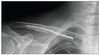

Dostal jsem tady tohle, není to přímo můj klíček, jen fotka z netu, ale moc se to od toho co jsem viděl včera na rentgenu neliší. Při vyšroubování stačí jen malý řez v místě konce šroubu (cca dva stehy) a vydělá se to ven. podle hmatu cítím, že kosti jsou přesně u sebe.

0 0